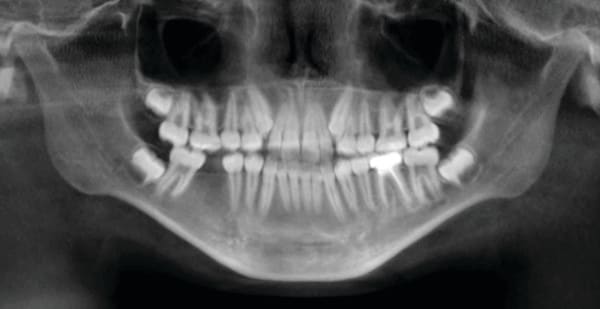

5. Any case that needs expansion of the maxilla. 3D imaging in these cases allow the orthodontist to determine if a cross bite is skeletal or dental. The clinician can readily determine if the molars are inclined in a cross bite or if the entire maxilla is constricted. This in turn can determine what forces are desirable to correct the cross bite. The 3D images also allow the clinician to evaluate the amount of bone around the roots of the teeth that are to be expanded. This also can aid the orthodontist in the type of forces to be utilized. Maybe bone augmentation is indicated in certain areas so as the roots are not once again fenestrated through the cortical bone creating a less stable environment. See Figure 18 through Figure 25. Figure 18 illustrates a maxilla that is constricted due to a narrow maxilla. Figure 19 illustrates the maxilla after expansion. Figure 22 illustrates a molar being tipped lingually. Thus a unilateral cross bite appliance was utilized.